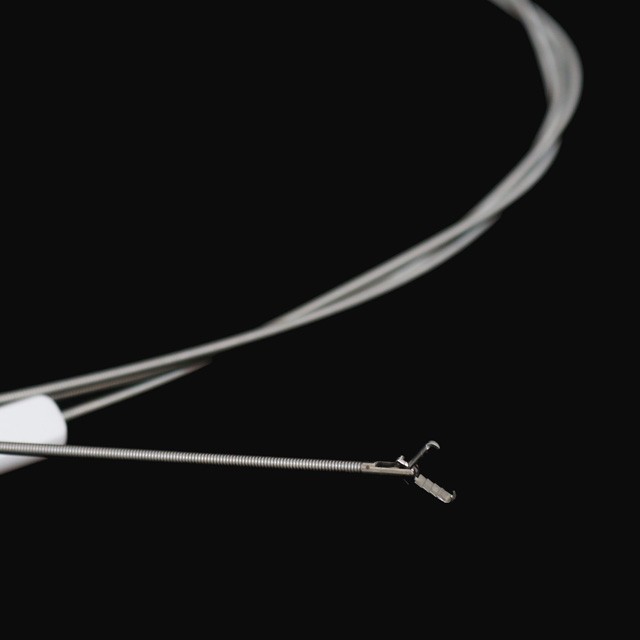

Prong tipe

|

Model |

Skede o . d . |

Werkende kanaal |

Werkslengte |

Funksies |

|

Fg -28 u-b3 |

2.3 |

Groter as of gelyk aan 2,8 |

2300 |

3- prong tipe |

|

Fg -28 u-b4 |

2.3 |

Groter as of gelyk aan 2,8 |

2300 |

4- prong tipe |

|

Fg -28 u-b5 |

2.3 |

Groter as of gelyk aan 2,8 |

2300 |

5- prong tipe |